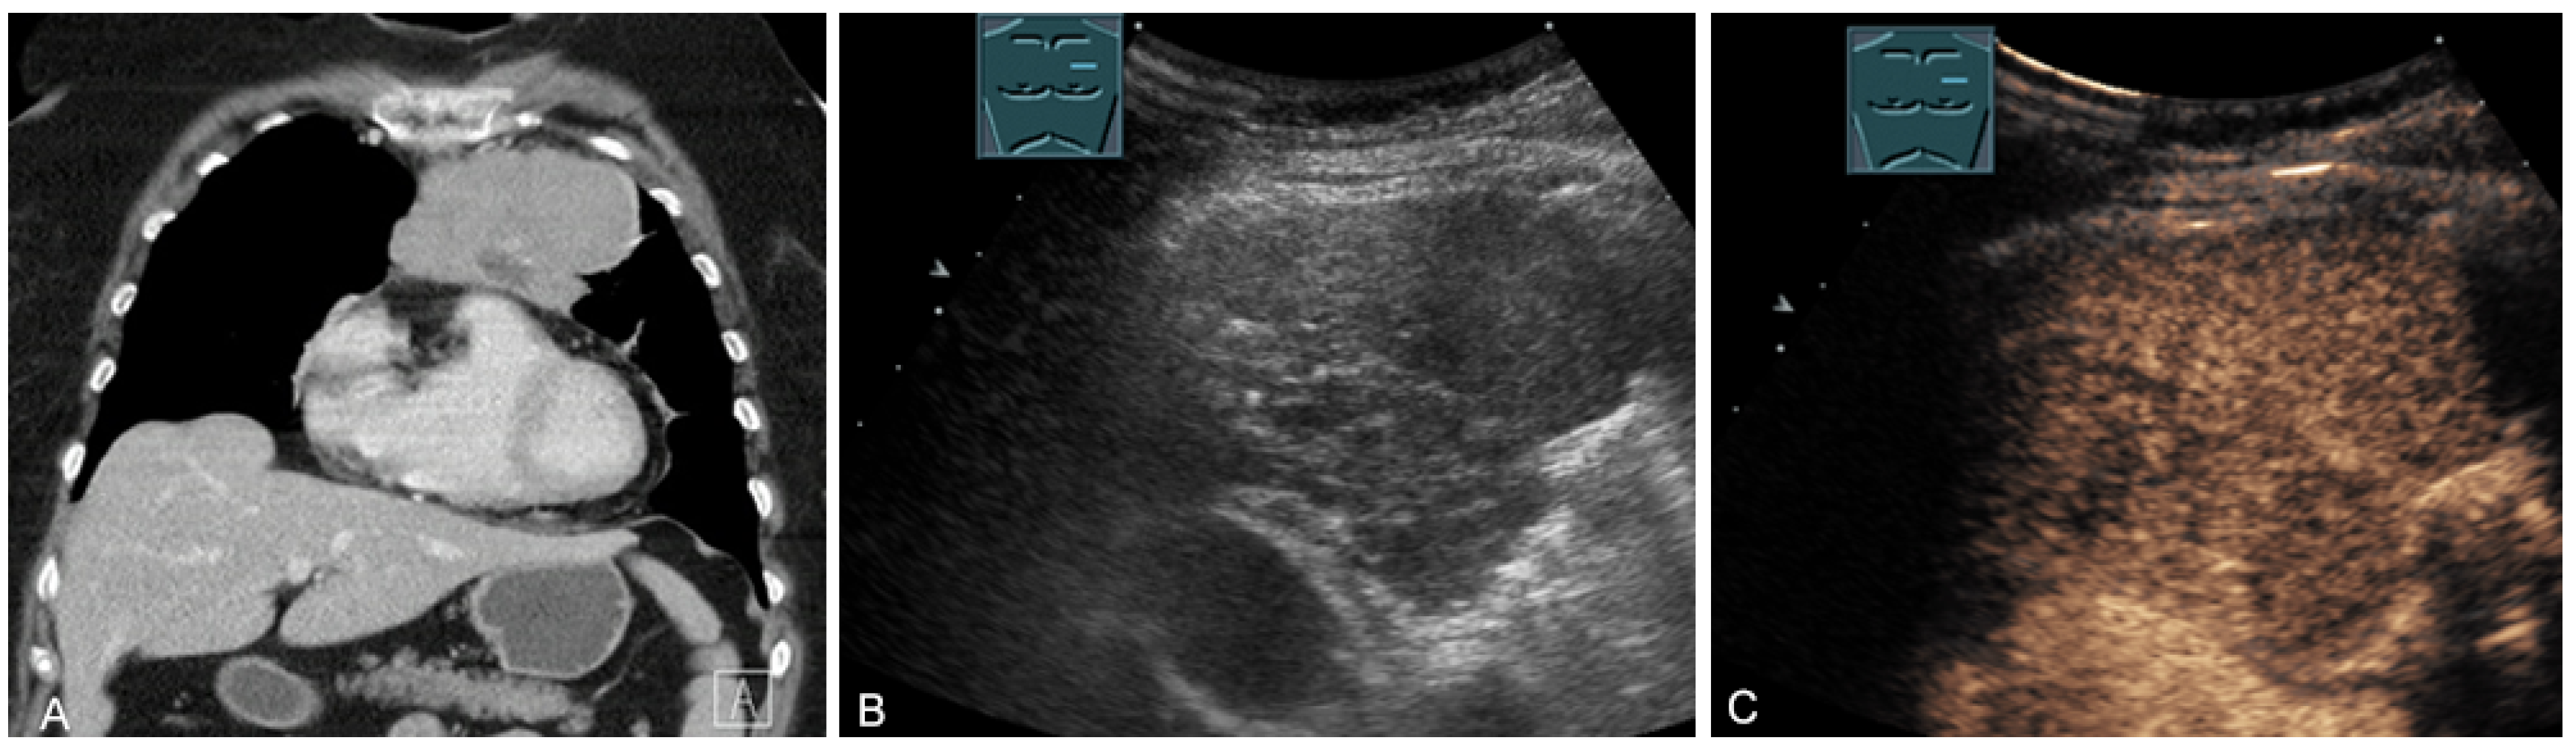

Figure 22.

A patient with tumor formation in the anterior mediastinum on CT (provided by Prof. Dr. Andreas H. Mahnken, Marburg, Germany) (A), B-mode US (B), and CEUS (C), confirmed by biopsy as diffuse large B-cell non-Hodgkin’s lymphoma.

Figure 23.